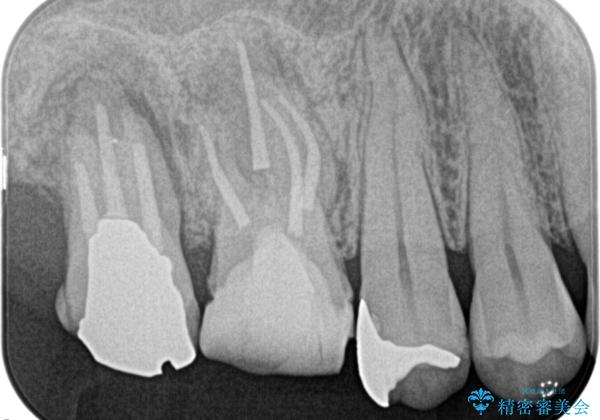

湾曲根管。精密根管治療

- 主治医から補綴前に根管治療を紹介いただいた患者様です。

検査の結果、右上第一大臼歯の診断を、歯髄壊死とし抜髄を行っております。

- 精密根管治療(イニシャルケース,大臼歯):122,000円、ファイバーコア:22,000円費用は治療当時の料金となります

湾曲根管に対してエラーなく処置を行えております。